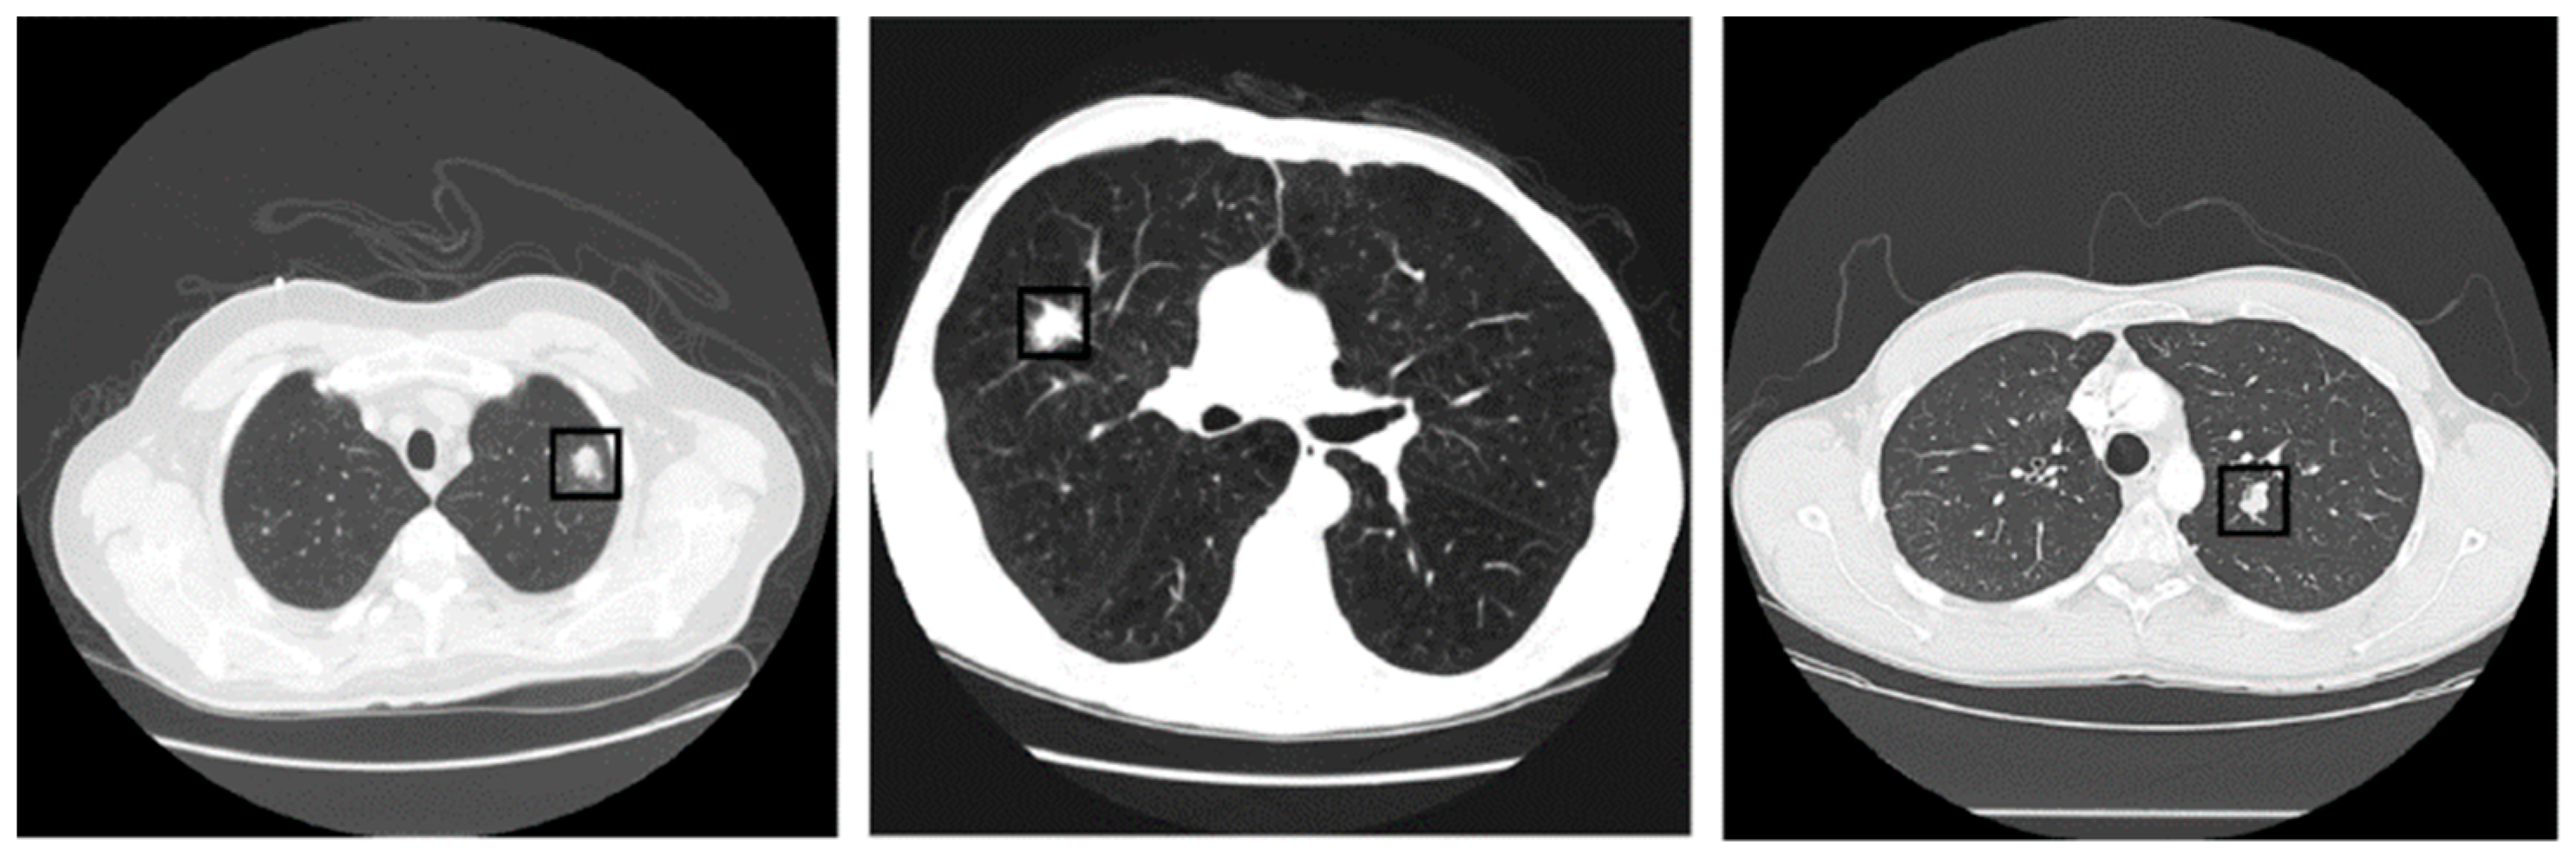

Automated Lung Nodule Detection and Classification Using Deep Learning Combined with Multiple Strategies